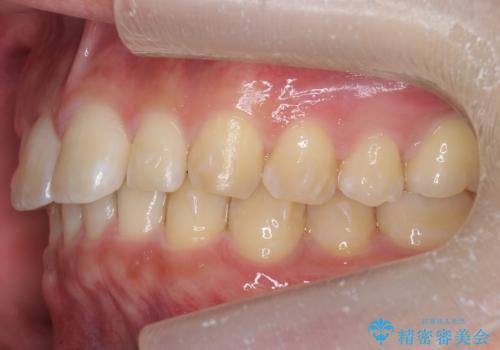

矯正治療で1番目の歯を寄せて2番目の歯はセラミックで形をととのえています。

上下のかみこみがきつい場合で上にだけすき間がある場合は、上のすき間を閉じきるのは難しいことが多いです。

理由としては、すき間を閉じるには上の前歯は後ろに下がる形に動かないと無理なのですが、かみこみがきつい(かみ合わせがきつい、上下が深く咬んでいるともいいます)場合は、すぐ後ろに下の歯がかみこむためその動きができないためです。

さらに下の前歯にがたつきがある場合は下の前歯を後ろに下げること自体が難しくなるため、生まれつき歯の形が特殊な場合は、上のすき間を適切な位置にずらして、しかるべき歯にセラミッククラウンを被せて形態修正とスペースを埋めるというのが効率の良い治療方法と言えます。